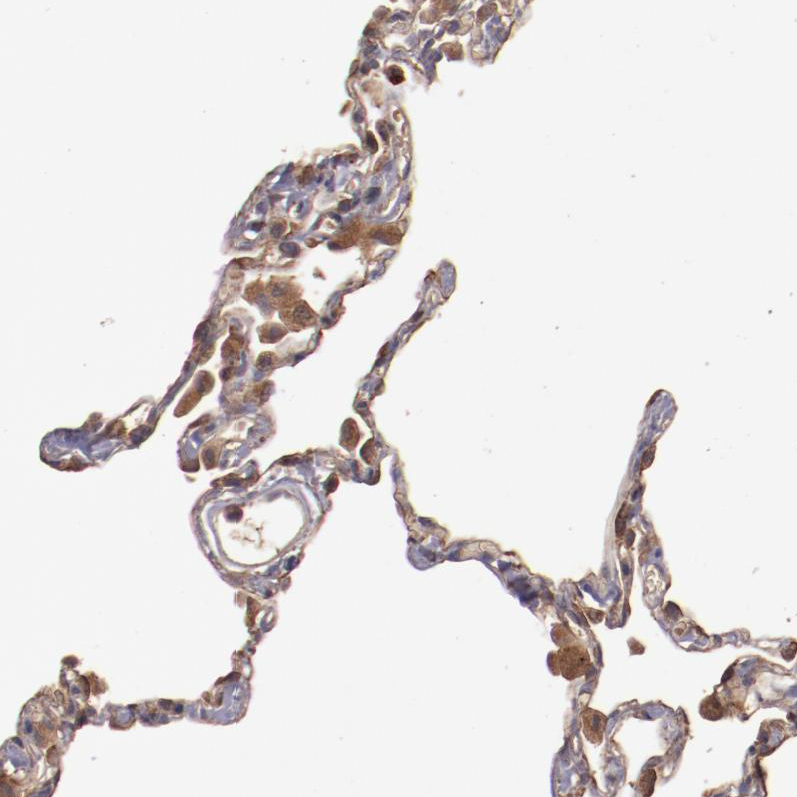

Immunohistochemical staining of human lung shows moderate cytoplasmic positivity in pneumocytes and alveolar macrophages.